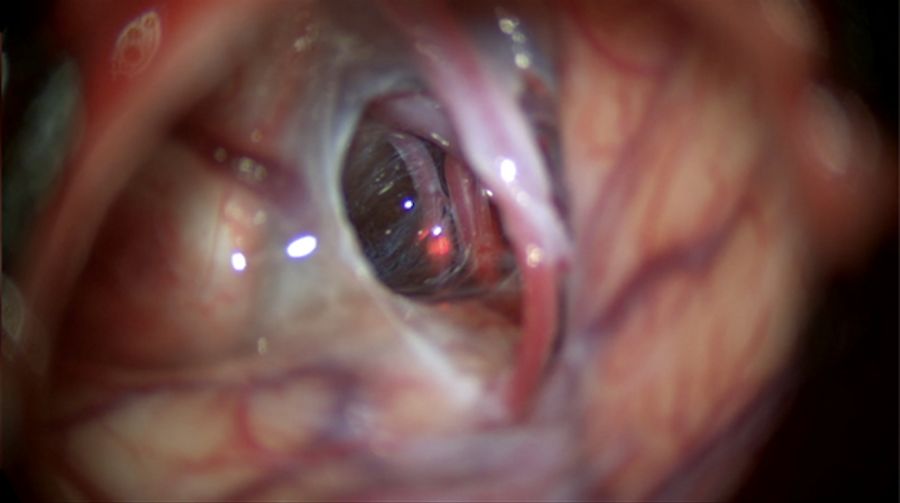

A 4-cm semi-curved incision centered on the left temporal region was performed, after which a musculocutaneous dissection of the temporal muscle was performed, and self-retaining retractors were used to expose the pterion. A minipterional craniotomy of 3.5 cm was performed to access the cyst and the basal cisterns. After opening the dura mater, a thick cyst wall could be visualized. The lateral cyst wall was resected to gain access to the contents of the cyst.

After the drainage of the cyst fluid, the medial wall could be seen compressing the temporal and frontal lobes. The inner wall was fenestrated with blade #11 to connect the cyst with the Sylvian cistern.

Once the Sylvian fissure was opened, the middle cerebral artery was exposed.

After opening the Sylvian and carotid cisterns, the membrane covering the carotid oculomotor space was opened and fenestrated with a curved microscissor, exposing the posterior communicating artery (Fig. 5).

Fig. 5: Removal of the membrane from the carotid oculomotor and exposing of the posterior communicating artery.

After being exposed, the Liliequist membrane was opened to connect the cyst to the interpedicular membrane (demonstrated in Video 6).

Once the fenestration and connections were completed, it was possible to have a complete view of the left carotid artery with the posterior communicating and choroidal arteries above the dorsum sellae (Video 7).

During the entire treatment of the arachnoid cyst, it was essential to have a realistic threedimensional picture of the cyst's anatomy and location. The M530 OHX surgical microscope ensured a brightly illuminated view and excellent color representation, which allowed me to easily differentiate between brain tissue and membranes, as well as apply my surgical skills precisely and efficiently. While working through the eyepieces, I had an optimal view, thanks to FusionOptics providing a clear and fully focused view without having interruptions due to refocusing. I could easily see brain and vascular structures to proceed with the drainage of the cyst by dissecting, connecting, and fenestrating the membranes, even in deep cavities.

Reliable images and illumination

During the dissection of the Liliequist and interpeduncular membranes, which are almost transparent, the Leica optics of the M530 OHX delivered a crisp image in natural colors, which helped to distinguish between layers more easily. The illumination of the M530 OHX provided a clear view and the light reflection from the transparent membranes made it easier to perform dissection. In addition, the liquid that had accumulated in the cyst was clearly visible in the cyst.

Deep Insights with the Small Angle Illumination (SAI) of the M530 OHX

SAI combined with bright 400-Watt xenon light provides a concentrated light beam that penetrates to the bottom of deep, narrow cavities. The result is better illumination with less shadow. SAI provides visualization of more

details and an improved depth perception.